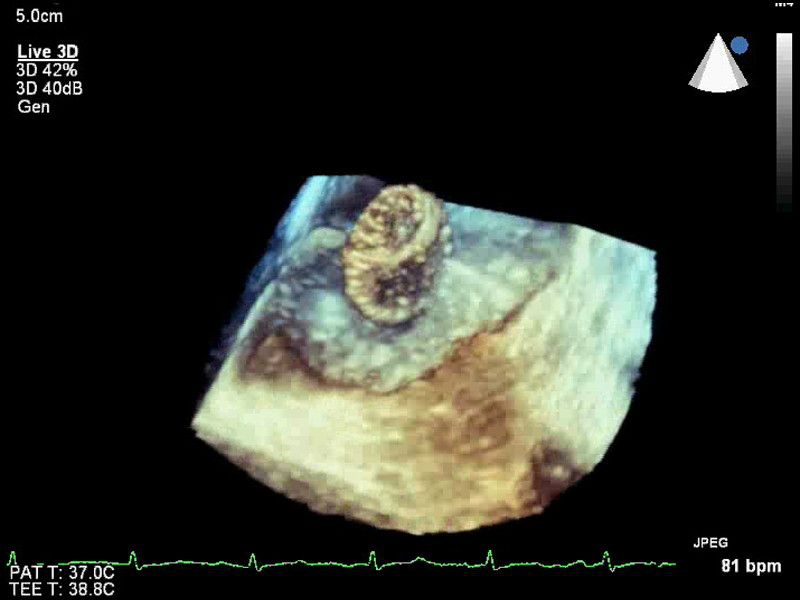

• Live 3D TEE: Эта функция позволяет проводить чреспищеводную эхокардиографию в режиме реального времени, что позволяет оценить механические сокращения сердца с точностью, необходимой для оценки результатов хирургического вмешательства.

• Live 3D Echo: Эта функция позволяет получать объемные 3D-изображения анатомии и механики сердца в режиме реального времени, расширяя возможности эхокардиографии.

• 3D эхо-кг в реальном времени (Live3DEcho): Эта технология позволяет получать объемные 3D изображения сердца в режиме реального времени.

• Live Volume: Эта функция позволяет получать объемные 3D изображения сердца в реальном времени с возможностью настройки скорости сканирования.